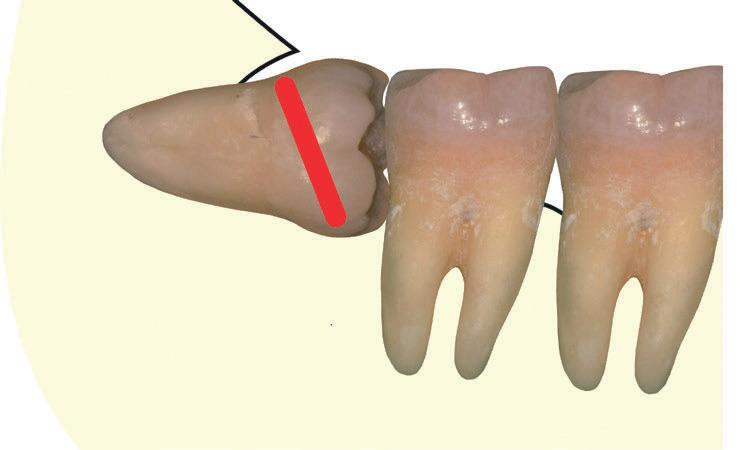

Questo schema illustra la quantità di dente rimosso (sezionamento della corona), l’angolo di accesso e la direzione dell’estrazione del dente. Fig. 139

Il blu indica la quantità di dente rimosso quando esso viene sezionato orizzontalmente, mentre il rosso quando è sezionato verticalmente.

Fig. 139 - Questo schema illustra la quantità di dente rimosso (sezionamento della corona), l'angolo di accesso e la direzione dell'estrazione del dente.